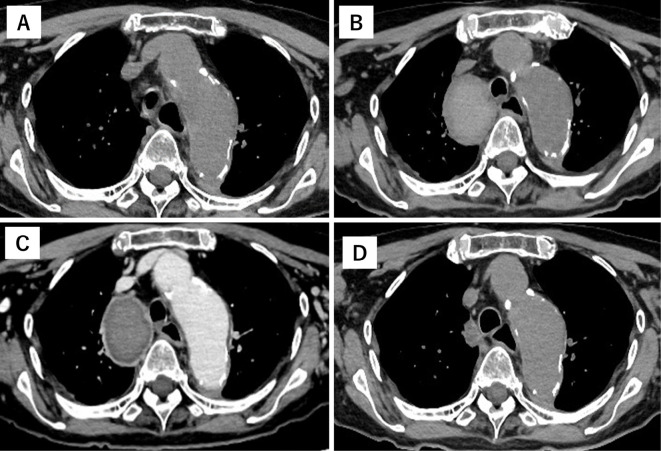

迅速增大的奇静脉动脉瘤伴血栓形成。

A Rapidly Enlarged Azygos Vein Aneurysm with Thrombosis.